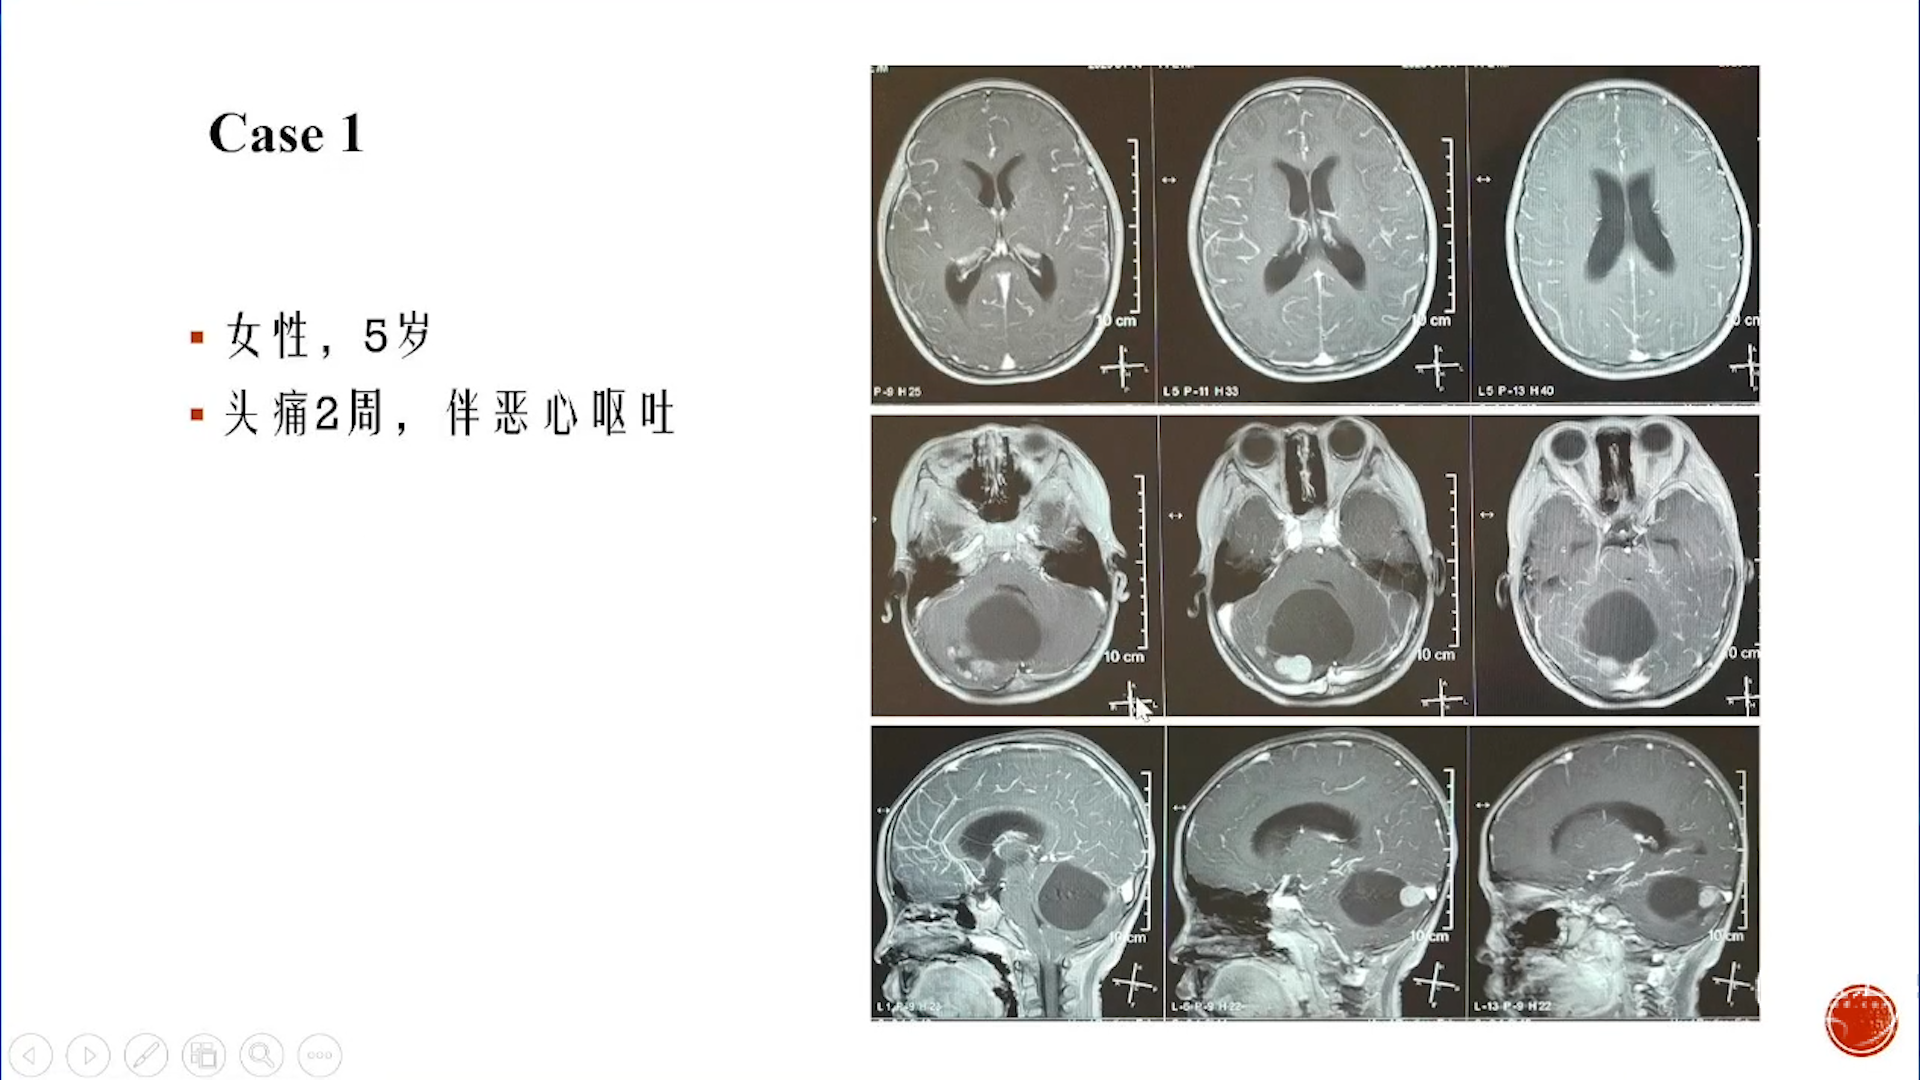

小脑星形细胞肿瘤